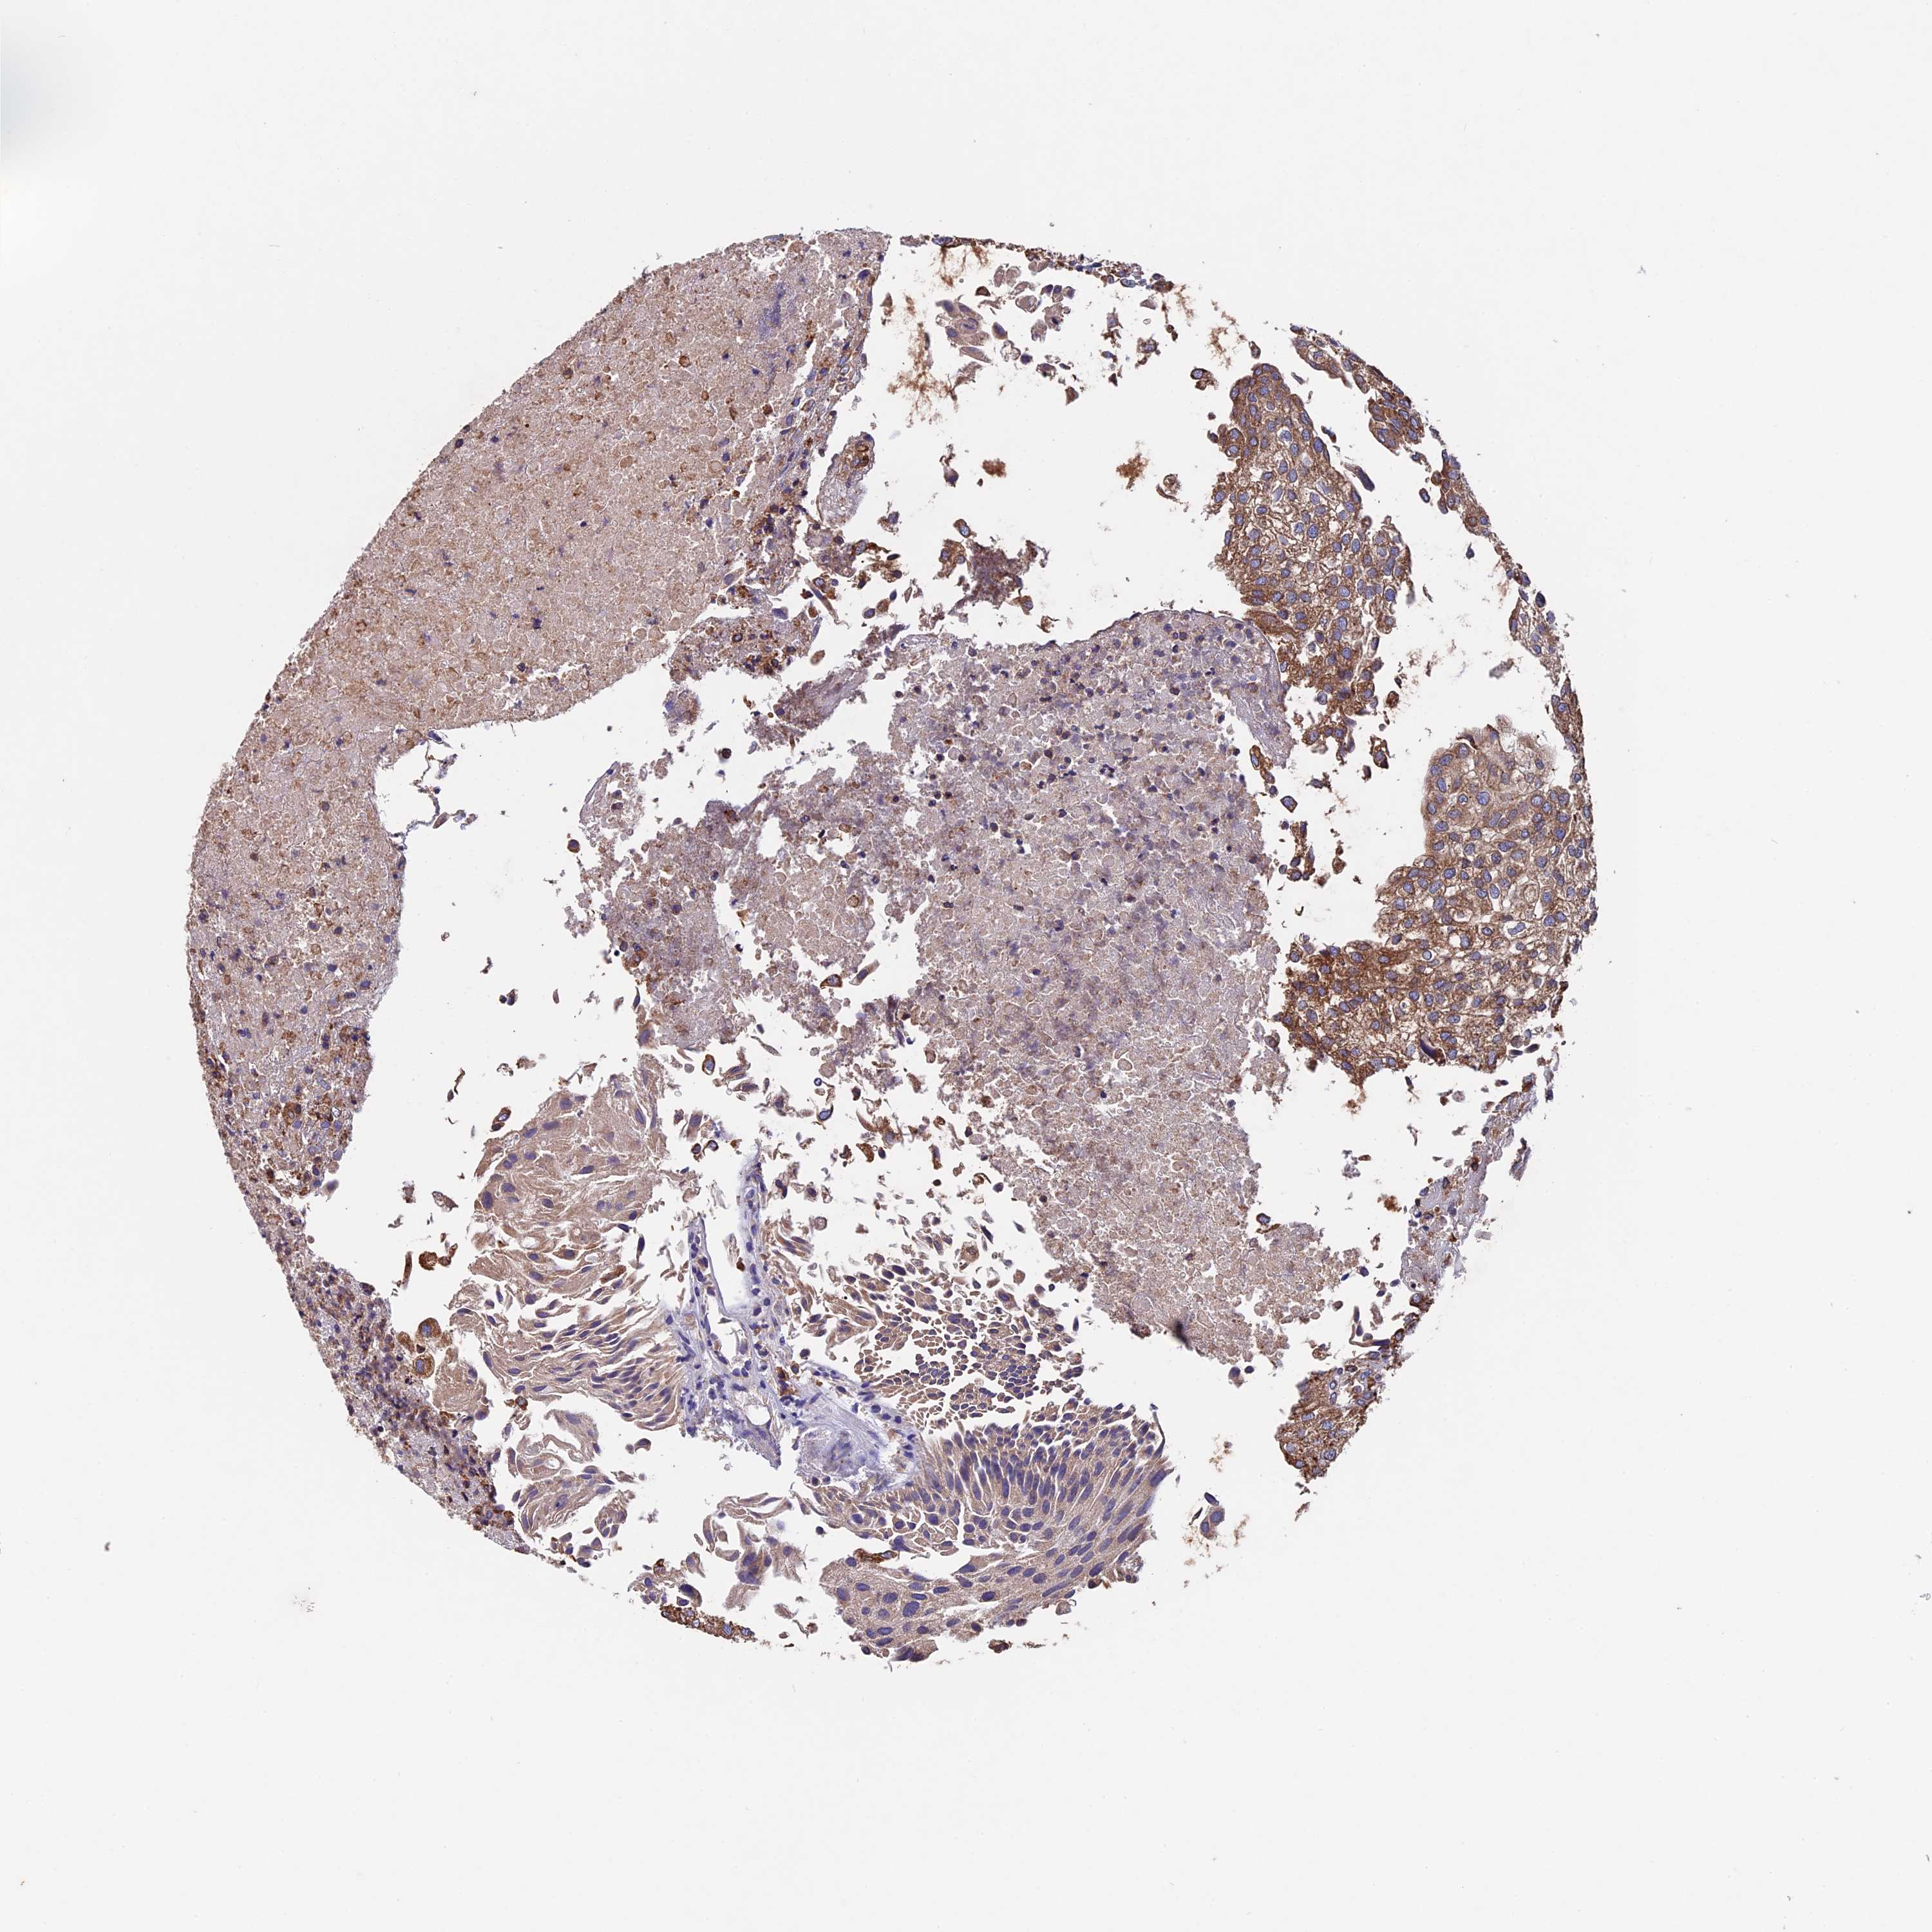

UROTHELIAL CANCER - Protein expressioni

A mouse-over function shows sample information and annotation data. Click on an image to view it in a full screen mode. Samples can be filtered based on level of antibody staining by selecting one or several of the following categories: high, medium, low and not detected. The assay and annotation is described here.

Note that samples used for immunohistochemistry by the Human Protein Atlas do not correspond to samples in the TCGA dataset.

Antibody stainingi

Antibody staining in the annotated cell types in the current human tissue is reported as not detected, low, medium, or high, based on conventional immunohistochemistry profiling in selected tissues. This score is based on the combination of the staining intensity and fraction of stained cells.

Each image is clickable and will lead to virtual microscopy that enables deeper exploration of all samples and also displays staining intensity scores, fraction scores and subcellular localization as well as patient and tissue information for each sample.

Antibody HPA041424

Antibody HPA042048

Urothelial carcinoma, High grade

Urothelial carcinoma, Low grade